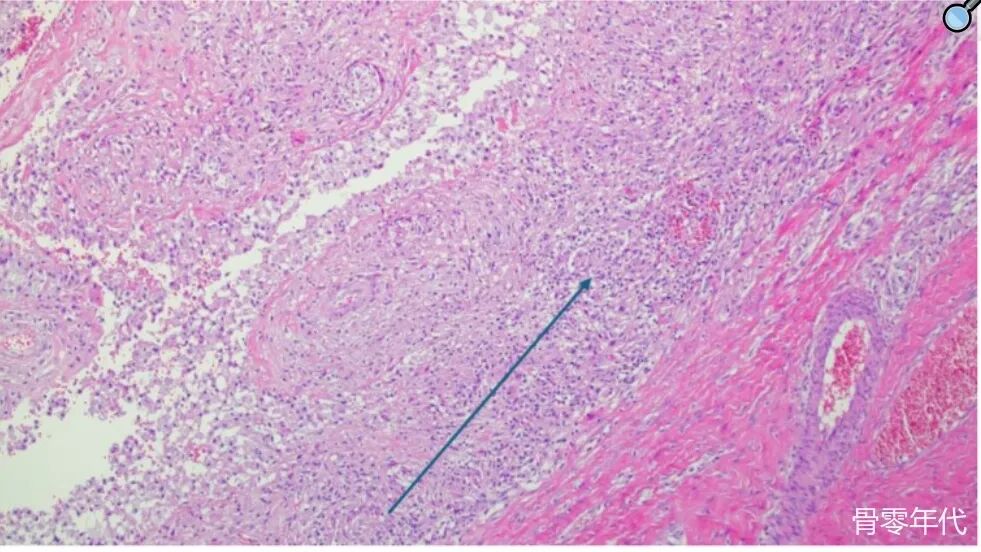

显微镜图像,带有H和E染色,描绘慢性炎症性组织巨噬细胞。箭头指向大量单核细胞的积累(×10倍放大)。